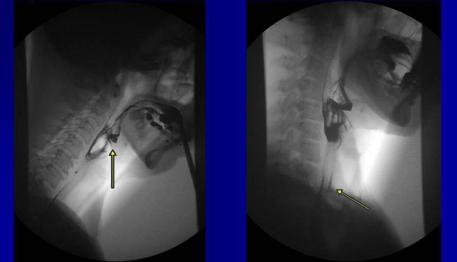

Videofluoroskopické vyšetření umožňuje detailní dynamické zobrazení průběhu polykacího aktu především ve fázi orální a faryngální. Odpovídá na otázku, proč má pacient poruchu polykání, a je základem pro správné zacílení terapie logopedické či chirurgické. Z vyšetření lze odvodit místo a čas spuštění polykacího aktu a trvání jeho jednotlivých fází, jako i jejich vzájemnou návaznost.

Videofluoroskopické vyšetření polykacího aktu

- Kontrastní RTG vyšetření odvozené od RTG polykacího aktu, nikoli jeho náhrada

- Dynamicky zobrazuje mechaniku polykání

- Odpovídá na otázku "Kde leží příčina poruchy polykání pacienta?"

- Penetrace - průnik k.l. do larygu, ne však pod úroveň pravých hlasových vazů

- Aspirace -

průnik k.l. do dýchacích cest pod úroveň pravých hlasových vazů

- Kašel po aspiraci x Tichá aspirace